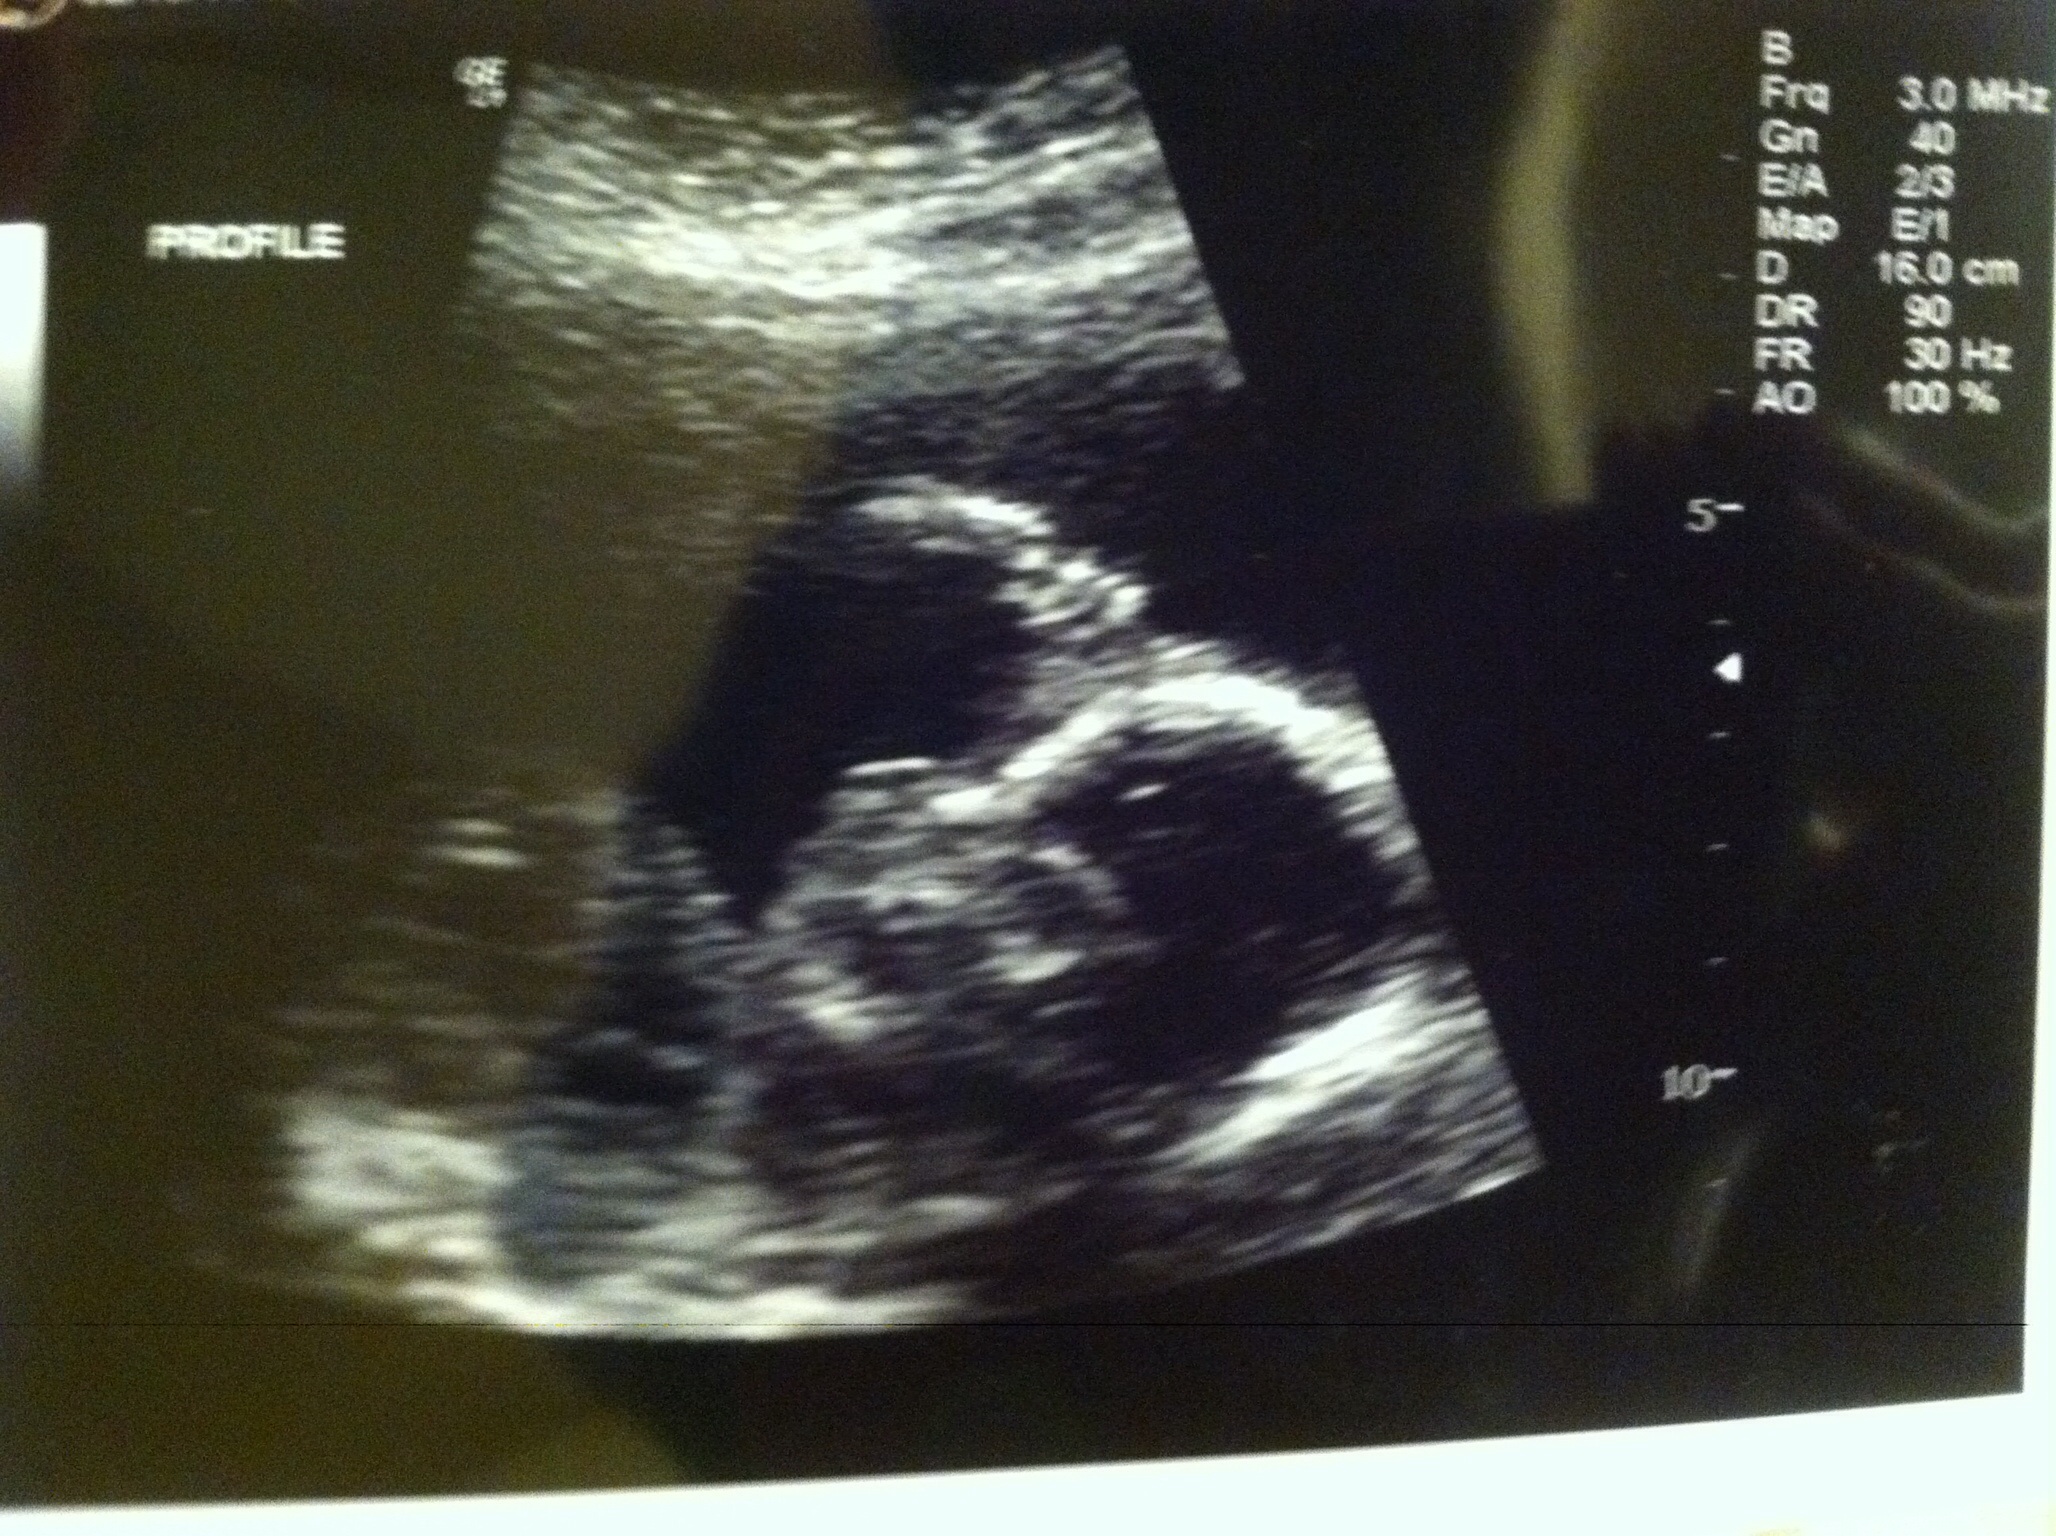

• Finally have a hdbd :-) 19wks2days.

you look great! and helloooo baby:)